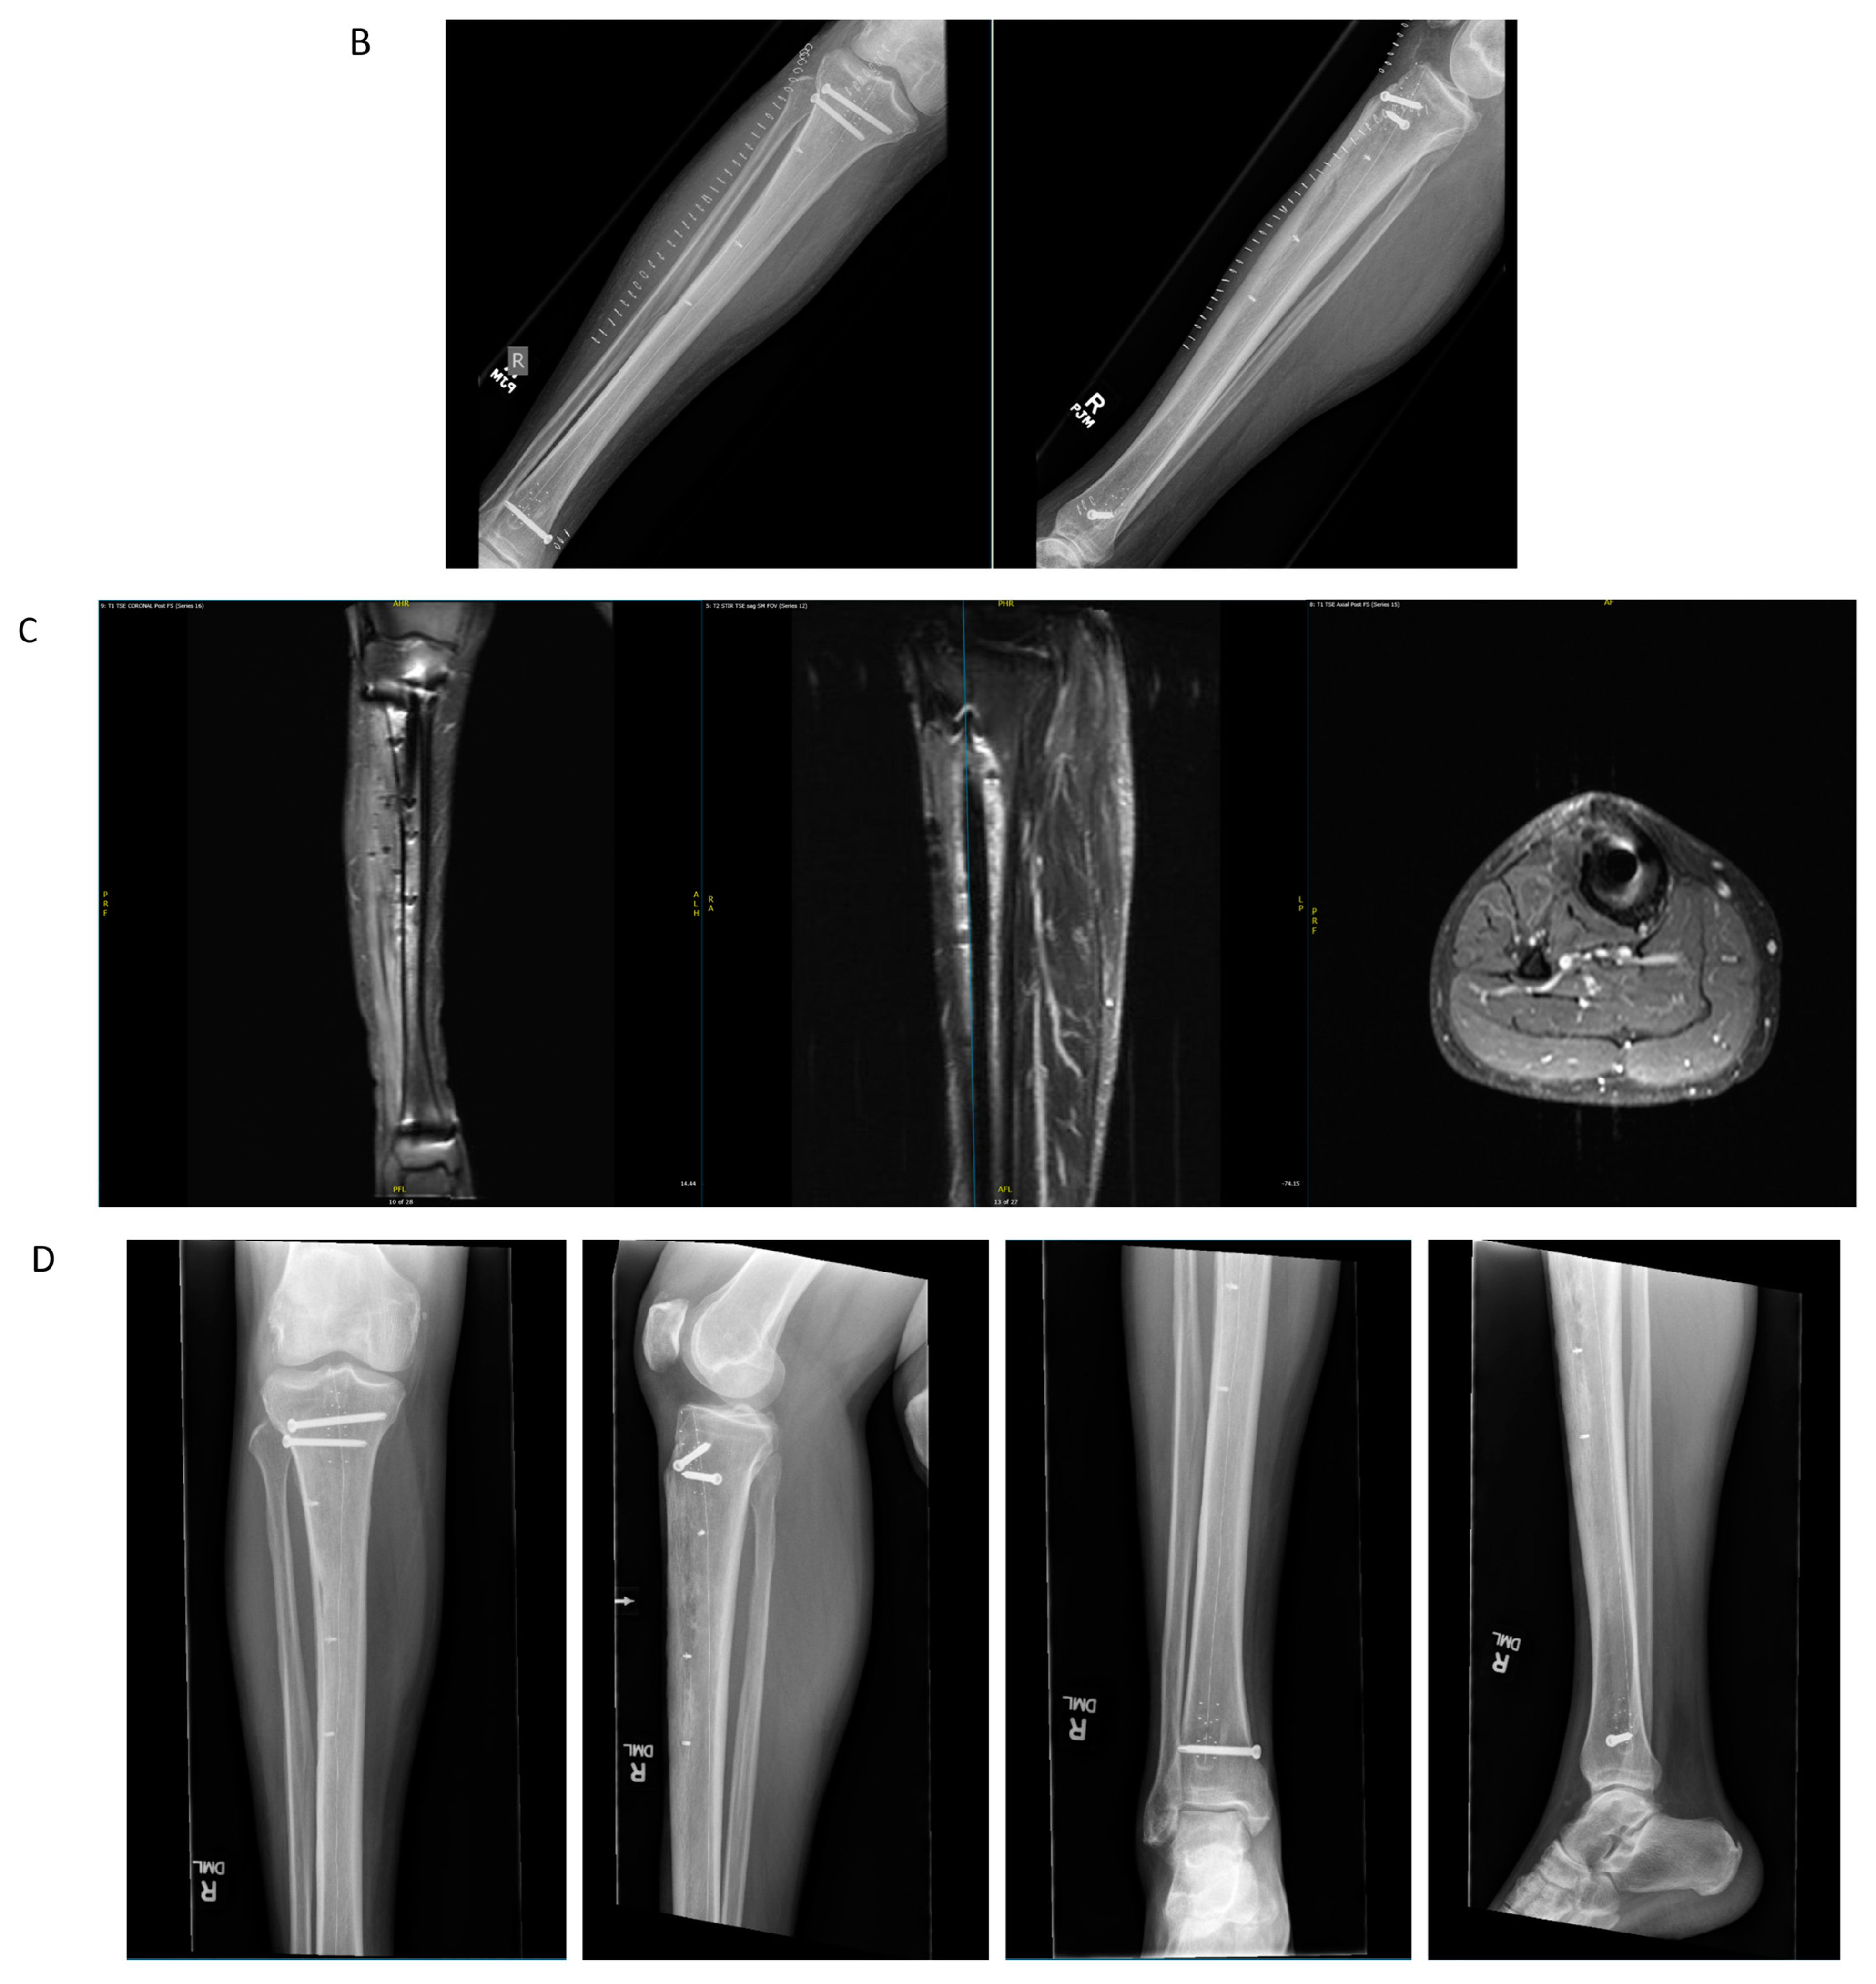

4.2. Case Example 2—Plate Fixation of Medial Femoral Condyle Osteoarticular Allograft following Medial Femoral Condyle Resection of Chondrosarcoma

4.3. Case Example 3—Plate and Intramedullary Nail Fixation of Allograft Reconstruction of Femoral Intercalary Resection of Chondrosarcoma